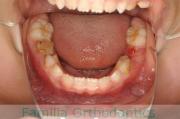

上の出っ歯、口が閉じにくい、下の前歯のガタガタを治したいということで来院されました。上顎から左右小臼歯を、下の前歯は凹凸が非常に強いので、こちらから一本抜歯を行いました。2年強、30回程度の通院が必要でした。

成人になってからの叢生(でこぼこ、凹凸、ガタガタ)は、保定をしっかりしないと後戻りをしてしまうリスクが高いです。

- ≫治療前

-

上顎

下顎

前歯の関係など

右側

正面

左側